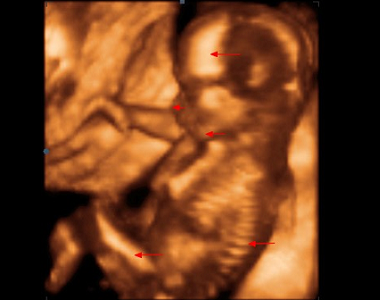

Druhý trimestr (14. týden těhotenství až 27. týden těhotenství)

Nejvýznamnějším v tomto období jsou pohyby plodu, které matka začne cítit kolem 20. týdne těhotenství, druho a vícerodička již kolem 18. týdne těhotenství. Jedná se o období rychlého růstu plodu a vývoje orgánů. Komplikace jako nevolnost začínají ustupovat, naopak se objevují ty, které souvisí se zvětšující se velikostí plodu.